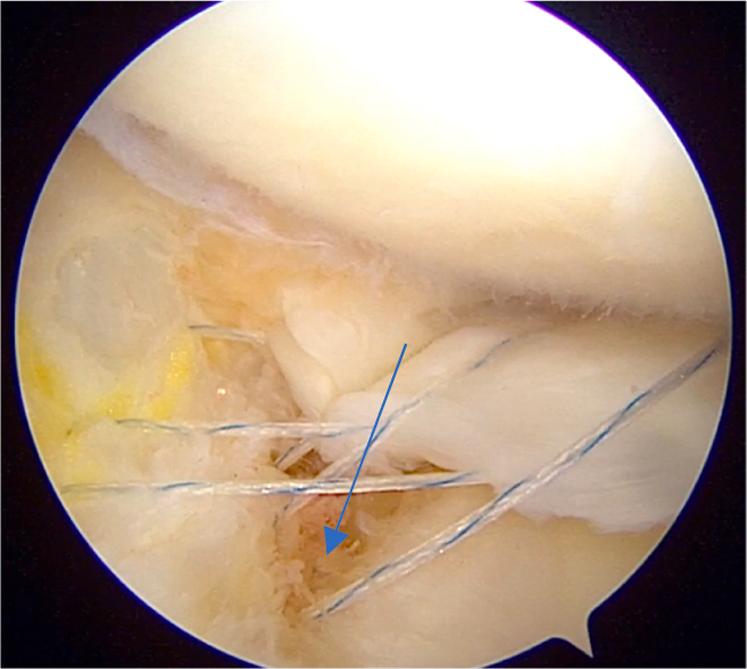

The meniscus plays a very important role in normal functioning of the knee joint. It acts as a shock absorber, gives stability to the knee joint, delays the onset of osteoarthritis, provides load sharing, and so on. It is a well-known fact that after meniscectomy, there is a significant increase in joint reaction forces leading to early osteoarthritis. Hence, in the past decade, meniscal repair has gain enormous importance and various techniques have been developed to repair the meniscus. Conventionally, posterior-third meniscal tears are repaired with all-inside and outside-in techniques whereas middle-third meniscal tears are repaired with all 3 methods: inside out, outside in, and all inside. For tears of the anterior horn of the meniscus, only the outside-in method is used. We have developed a method for repair of chronic unreduced, retracted bucket-handle anterior horn lateral meniscal tears, in which we combined the use of both the outside-in and all-inside methods of repair. Hence, this method is called modified outside-in meniscal repair for chronic retracted bucket-handle anterior horn lateral meniscal tears.

半月板在膝关节的正常功能中起着非常重要的作用。它充当减震器,为膝关节提供稳定性,延缓骨关节炎的发生,分担负荷等等。众所周知,半月板切除术后,关节反应力会显著增加,导致早期骨关节炎。因此,在过去十年中,半月板修复变得极其重要,并且已经开发出各种技术来修复半月板。传统上,后三分之一半月板撕裂采用全关节内和由外向内技术修复,而中三分之一半月板撕裂则采用三种方法修复:由内向外、由外向内和全关节内。对于半月板前角的撕裂,仅使用由外向内方法。我们已经开发出一种修复慢性未复位、回缩的桶柄状前角外侧半月板撕裂的方法,在该方法中,我们结合使用了由外向内和全关节内两种修复方法。因此,这种方法被称为用于慢性回缩桶柄状前角外侧半月板撕裂的改良由外向内半月板修复术。